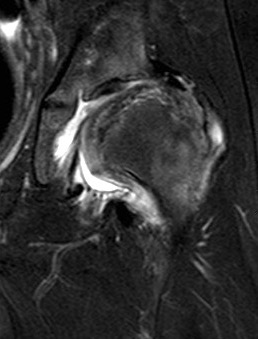

Femoral head reduction osteotomy (FHRO)

Concept

Misshapen femoral head

Open surgical dislocation

- remove central necrotic area femoral head

- rreposition lateral femoral head to medial femoral head

Results